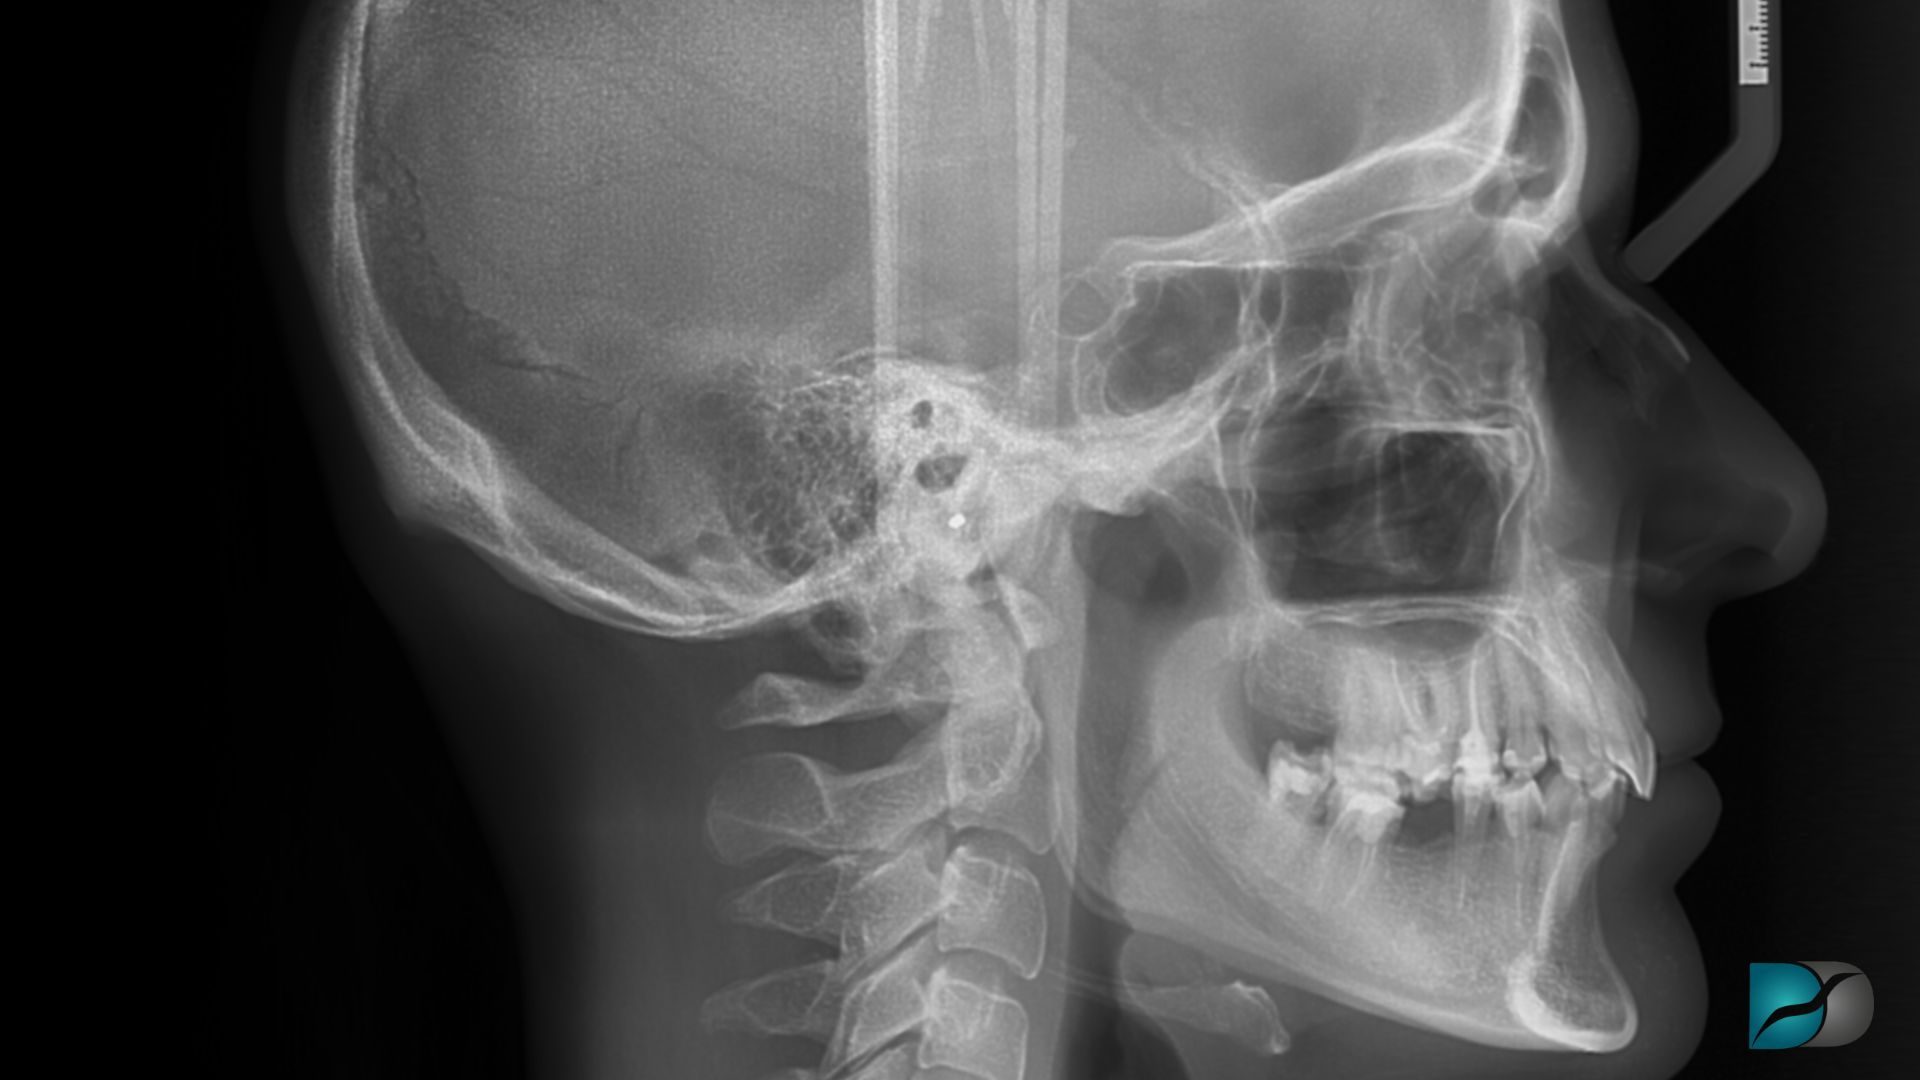

Le tracé céphalométrique avec intelligence artificielle (IA) séduit de plus en plus les orthodontistes grâce à sa rapidité et à la promesse d’analyses standardisées. Une étude récente publiée dans BMC Oral Health s’est penchée sur la question : ces outils automatisés peuvent-ils réellement remplacer les méthodes semi-automatiques et manuelles encore largement utilisées en cabinet ?

Depuis son introduction dans les années 1930, la céphalométrie constitue un pilier du diagnostic orthodontique, de l’analyse de croissance et du suivi thérapeutique. Longtemps réalisée de façon manuelle, puis digitalisée, elle est aujourd’hui en pleine mutation avec l’arrivée de solutions basées sur l’intelligence artificielle.

Ces logiciels permettent de détecter automatiquement les points anatomiques et d’effectuer les calculs en quelques secondes, réduisant ainsi la variabilité inter-opérateurs et la durée d’analyse. Pour autant, leur fiabilité fait débat dans la littérature scientifique, certaines études évoquant des imprécisions en raison d’erreurs d’identification des repères anatomiques.